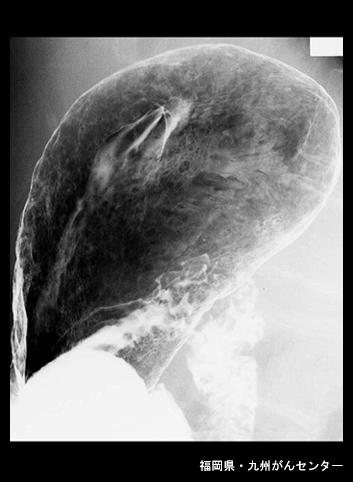

Posted by: Fukuoka Pref., National Hospital Organization Kyushu Cancer Center

Criteria of Hist.ClassificationMalignant epithelial tumor/Adenocarcinoma

LocationStomach/More than one of above

Technique, MethodX-ray

Macroscopic TypesType 5 Unclassfied type/

Size40 -

Depth of Tumor Invasionsubserosa (subadventitia)